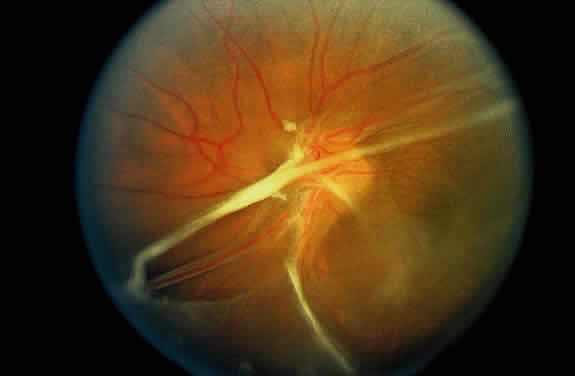

As a result of the retinal nonperfusion, new vessels can form either on the disc (neovascularization of the disc) or, more commonly, neovascularization can occur elsewhere in the retina (Fig. 5). These abnormal blood vessels can hemorrhage and are the major cause of visual loss in this disease. The neovascularization in the peripheral retina usually occurs at the junction of perfused and nonperfused retina, similar to the appearance of neovascularization in the peripheral retina in diabetic retinopathy and the other peripheral proliferative retinopathies. Neovascularization can be associated with extensive fibrovascular proliferation and fibrosis (Fig. 6). The anteroposterior and tangential traction resulting from the fibrovascular proliferation places these eyes at risk for development of retinal detachment. Neovascularization of the iris also has been described.

Fig. 5. Neovascularization of the peripheral retina has developed at the junction of perfused and nonperfused retina.

Fig. 6. Hypovascular fibroproliferation emanating from the disc. Usually, the vascular component of this proliferation is less prominent than that seen in the other proliferative retinopathies. Notice the tractional retinal detachment.